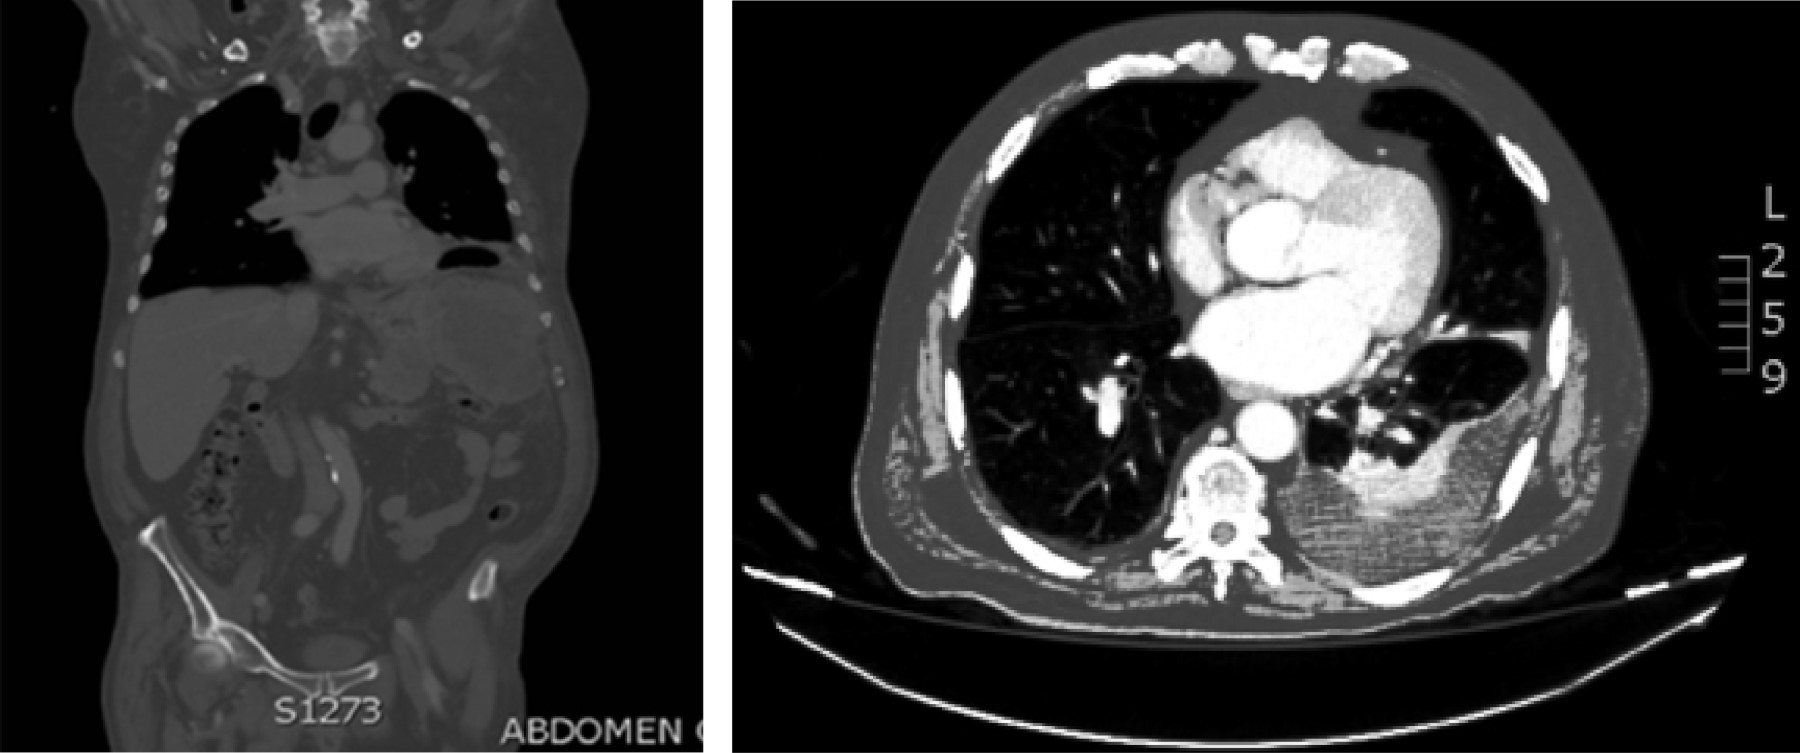

Introducción: La prevalencia de cáncer gástrico en México ha tenido un incremento en los últimos años con predominio en hombres. Los factores de riesgo son el consumo de alcohol, tabaco e infección por Helicobacter pylori, considerado en nuestra población como de riesgo moderado. Aunque el adenocarcinoma sigue predominando como la neoplasia maligna gástrica más frecuente, un porcentaje no despreciable del 7-8%, según la Organización Mundial de la Salud, lo ocupa el linfoma no Hodgkin (extranodal) y los leiomiosarcomas. El adecuado abordaje diagnóstico y la diferenciación son cruciales entre el adenocarcinoma y el linfoma, ya que de ello depende el pronóstico y el tratamiento. Caso clínico: Se comunica el caso de un hombre de 79 años con astenia, hipercalcemia maligna con hallazgo incidental de engrosamiento gástrico por tomografía. Se realizó ultrasonido endoscópico para el diagnóstico de linfoma gástrico de variedad difuso (Ann Arbor modificada II2). Revisión de literatura: El ultrasonido endoscópico es considerado una herramienta para el diagnóstico de neoplasias malignas gástricas en todas sus variantes, principalmente donde la enfermedad se encuentra en capas profundas. Conclusión: El ultrasonido endoscópico es el método que nos lleva a obtener alta precisión diagnóstica en linfoma gástrico permitiendo la toma de biopsias del espesor total de la pared de bloque celular para realizar diagnóstico diferencial siempre con inmunohistoquímica.

Figura 1